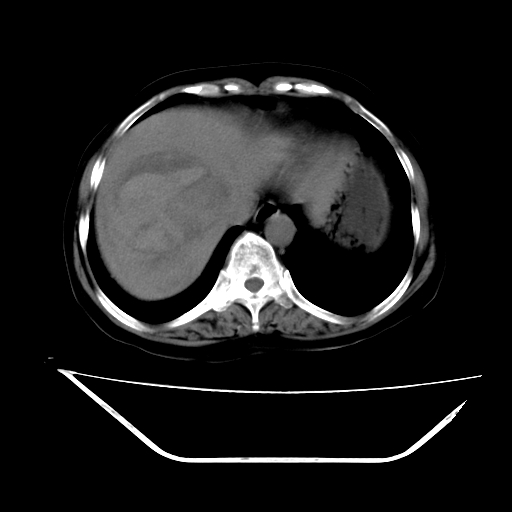

2008-11-10ct平扫(其间去中山医院诊治未行特殊治疗)

2008-11-10ct平扫见并肝内、血膜下血肿基本吸收,肝内低密度灶缩小。此时再做增强ct应有显着意义。对患者/医者都好!

从平扫+增强及治疗后复查片,病变明显缩小,不考虑肝癌出血可能,还是考虑为良性病变可能性大;单纯血肿并包膜下积液吧,病变强化没法解释,肝血管破裂出血吧,增强不符合典型血管瘤的表现,良性肿瘤破裂出血吧,复查片看来好像也不太支持(没做强化也不太好说)。本人还是考虑单纯肝内血肿并包膜下积液,强化是不是血管有外渗。

患者自6月至11月,如果是肝癌,没有经过特殊治疗,想必应该会有所进展吧,而不是ct所见,反而似有病灶减小的趋势。建议增强。

追问病史,患者有过度用力病史,当时立即感腹痛;所以还考虑肝破裂可能性大。